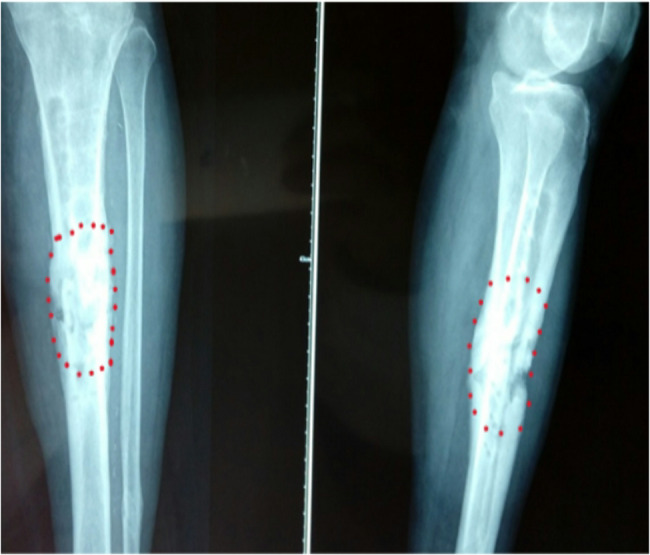

Methods: Seventy patients with Cierny-Mader stages III and IV chronic osteomyelitis admitted to the Department of Orthopedics of a Class III Grade A Hospital from January 2018 to March 2022 were selected for retrospective analysis and study. The following patient data were collected: gender, age, site of infection, bacterial culture results, internal fixation status, bone defect length, BMI, history of diabetes mellitus, smoking history, and history of preoperative antibiotic use. The patients were treated with sensitive antibiotics after surgery, followed up regularly, and venous blood C-reactive protein (CRP), sedimentation (ESR), white blood cells (WBC) and muscle strength (MTT scale), joint mobility (neutral 0° method), and bony healing time were measured to observe the recurrence rate of osteomyelitis and to assess the recovery of limb function according to the Enneking scale.

Results: Among the 70 patients, 20 cases were guided by X-ray, 30 cases by MRI, and 20 cases by SPECT. All patients underwent thorough debridement under the guidance of imaging modalities followed by external fixation. All cases were followed up and with a mean follow-up time of (12.2 ± 3.2) months. The recurrence rate of 35% in patients with X-ray as a guide was significantly higher than that of patients with MRI as a guide (10%) and SPECT as a guide (5%), and the difference between the three groups was statistically significant (P < 0.05).

Conclusion: For patients with osteomyelitis without metal internal fixation, the osteotomy surgical technique with MRI to guide the expansion of 0.5 cm distally and proximally, or with SPECT imaging to guide the surgical procedure in the area with 30-40% of the radioactive count contour (isocontour, ISO) had the advantages of low recurrence rate and good recovery of limb function, and the differences were not statistically significant. For patients with osteomyelitis with metal internal fixation, the osteotomy surgical technique with SPECT to guide the surgical procedure had the advantages of low recurrence rate and good recovery of limb function. In patients with osteomyelitis with metal internal fixation, SPECT was used as a guide to determine the extent of the osteomyelitis lesion, and osteotomy in the area with 30-40% of ISO was more effective than MRI.